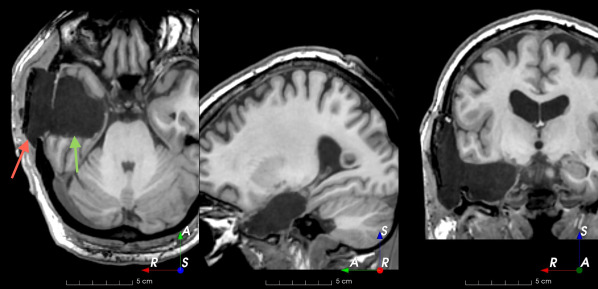

(f)

Figure 3: Manual labels from Rater A (green) and Rater D, the model trained with PubFull + EpiPre + Pseudo (magenta). Errors caused by a (a) small resection, (b) blood clot in cavity and (c) brain shift; segmentations corresponding to the (d) 50th, (e) 75th and (f) 100th percentiles giving a DSC of 81.7, 86.5 and 93.8, respectively.

We trained a model using PubFull, EpiPre and Pseudo (2371 images), obtaining a DSC of 81.7 (14.2). Adding the pseudo-labels to PubFull and EpiPre did not significantly improve performance (p=0.176𝑝0.176p=0.176), indicating our semi-supervised learning approach provided no advantage. Predictions from this model are shown in Fig. 3.

Predictions errors are mostly due to 1) resection of size comparable to sulci (Fig. 6a), 2) unanticipated intensities, such as those caused by the presence of blood clots in the cavity (Fig. 6b), 3) brain shift (Fig. 6c) and 4) white matter hypointensities (Fig. 6e). Further work will involve using different internal and external cavity textures, carefully sampling the resection volume, simulating brain shift using biomechanical models, and quantifying epistemic and aleatoric segmentation uncertainty to better assess model performance [24].